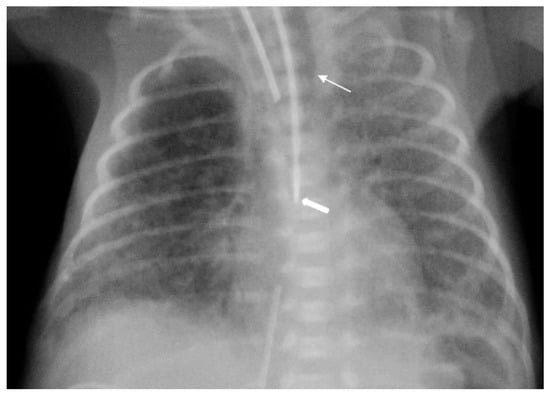

The diagnosis of EP was confirmed via the malposition of the og/ng tube in plain chest X-rays radiographic images. In infants with EP, the chest radiographic image revealed three different malpositions of the og/ng tube. In five infants, the og/ng tube was located in the right pleural cavity (pleural position) (Figure 1), which is usually connected with the pneumothorax or the pneumothorax with pleural effusion, and a radiogram of another two patients indicated mimic esophageal atresia (high position) (Figure 2). In the last three infants, the og/ng tube was located in the abdomen (low position) (Figure 3).

One patient had pneumothorax with pneumomediastinum, four infants had pneumothorax and another of them had milky pleural effusion.

The pleural location of the og/ng tube is usually indicative of a sudden deterioration of the respiratory function, while the low and high position are largely asymptomatic (apart from absence of gastric contents and blood aspiration). Patients with abdominal esophageal perforations may present signs of peritonitis. Mediastinitis may develop as a result of leakage of the esophageal contents.

Radiographs of the chest are useful in demonstrating the presence of the og/ng tube in situ and might reveal three different malpositions of the nasogastric tubes, typically in the right pleural cavity associated with right-sided pneumothorax or pneumomediastinum and sometimes pleural effusion. Common symptoms in this situation are connected with the deterioration of the respiratory status. A chest radiographic image may reveal excessive amounts of air in the mediastinum. The high position of the og/ng tube mimicking an esophageal atresia effect may be due to the presence of a mass created by a false passage of air or milk in the mediastinum [9,14]. The position of the top of the og/ng tube may be helpful in differential exclusion. In true esophageal atresia, it is usually above the bifurcation of the tracheae, while in the mimic esophageal atresia, it is located below the bifurcation. In doubtful cases, esophagoscopy can be conclusive [15]. The presence of gas along the og/ng tube may also be helpful in diagnosing EP. The third possible malposition of the og/ng tube involves the intra-abdominal location, which might be associated with the absence of gas in the intestines. It must be noted that a radiographic image cross-table lateral might, in this case, indicate where the tip of the og/ng tube would appear in the posterior/retroperitoneal space. This would be advisable for a more precise diagnosis. Another complication described by Sorens was mediastinal abscess requiring chest drain insertion [16]. Occasionally, patients with intra-abdominal EP might present symptoms of peritonitis or dysphagia and drooling [1]. In our study, like Elgendys’ study, pneumothorax and septicemia were frequent complications of esophageal perforation [17]. We diagnosed peritonitis in one patient and necrotizing enterocolitis in one patient. In one patient, cardiorespiratory decompression was connected to pleural milky effusion. Chylothorax should be considered and excluded upon differential diagnosis when milk is present in the pleural cavity and milky fluid can be aspirated from the right pleural cavity. Kairamkonda linked chylothorax with esophageal perforation, which may follow when the value of the laboratory fluid analyzed shows a triglyceride level of >1.1 mmol/l with absolute cell count > 1000 cells/mcl and lymphocyte fraction > 80% [18,19,20].

Figure 1. Large right tension pneumothorax with a mediastinal shift. A feeding tube is directed into the right pleura (arrow).